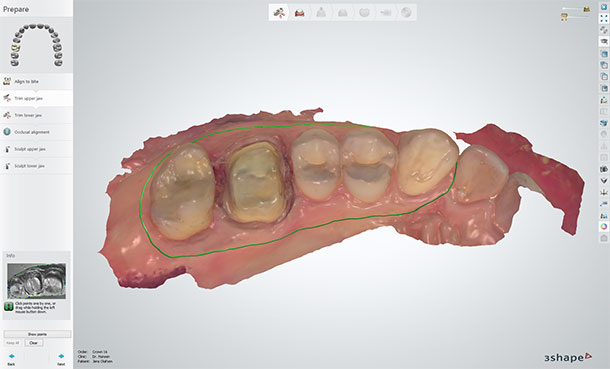

1.3 Prepare the scan before design - Trim the scan

The dentist may have trimmed the scan before sending the digital impression to your lab. However, it is important that you check the scan for excess material and remove any at this stage. I trim the model as much as I can and many dentists expect me to handle this part. Excess material in the scan can interfere with the bite registration and affect the accuracy of Virtual Articulation when you check the crown later on in the software.